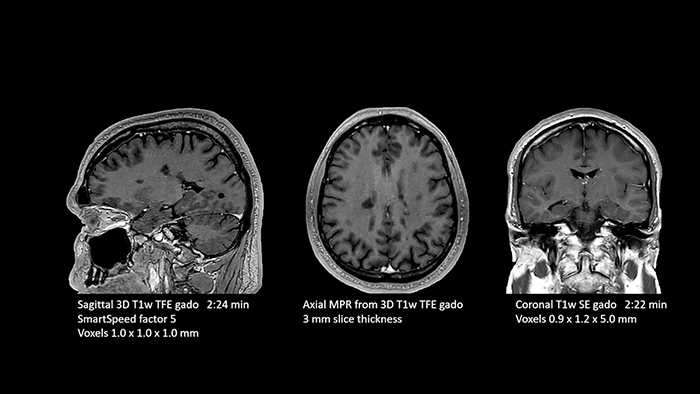

Dr. Schröter points out that a more confident diagnosis requires high-quality images with more diagnostic information. “Philips SmartSpeed provided that to us. AI denoises the clinical images without losing any important data, resulting in high-resolution images. It keeps all the information we need and makes the images better. We can apply SmartSpeed to almost all sequences. That is a big step forward! We use it for example in 3D imaging and in diffusion-weighted imaging, to dramatically reduce scan time or increase image resolution, which is quite useful. There are small lesions that we would certainly have seen without SmartSpeed, however it would have taken us longer to properly diagnose. In 3D MSK images with extremely high resolution, we uncover the finest anatomical structures and can thus report very detailed findings.”

In this examination SmartSpeed is used to reduce scan times. All three FLAIR orientations were obtained with only one 3D sequence using SmartSpeed. Performed with 1.5T Ambition X, dS Head coil.